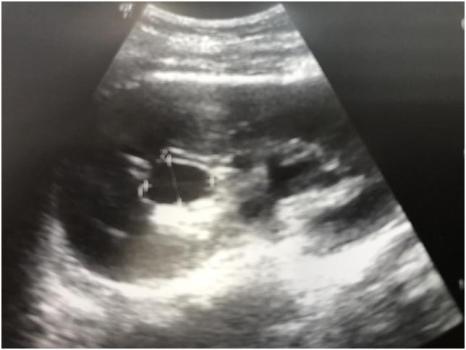

При УЗИ почек отмечается расширение всех групп чашечек максимальным размером до 25х17мм.

В устье левого мочеточника определяется гиперэхогенная тень размером до 6мм, (конкремент), дающая эхо-тень в виде акустической дорожки.